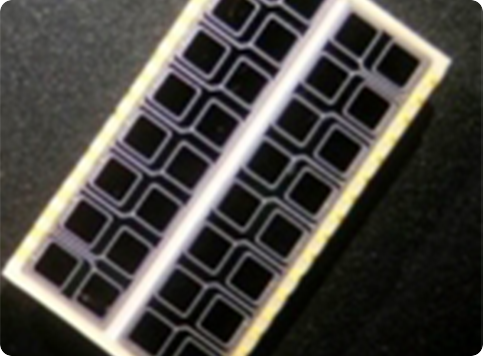

Several crystal-APD units and the corresponding frontend electronics are assembled in detector modules. Our APD-based detector module has 384 LYSO 2x2x20 mm crystals and covers a detection area of ~4x8 cm. One of the advantages the APDs is the capability of performing the double readout of the scintillation crystals, which allows to calculate the DoI of the detected photons. Associated to the fine detector pitch (2x2 mm) and the one-to-one coupling between crystal and APD pixels, the DoI capability permits an excellent spatial resolution of the order of 1.3 mm over the whole Filed-of-View.